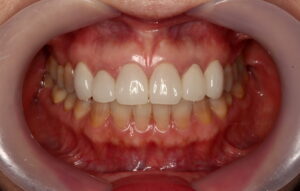

こちらはテトラサイクリン歯の1例です。

歯の1~2本だけでなく全体的な変色があるケースで審美的にマイナスになりがちです。

従来の方法では、ラミネートベニアやセラミッククラウンを行うために歯を削り、セラミック材料を被せて治す方法が主流でした。

今回は、削らないラミネートベニアでの治療についての症例写真となります。

削らないラミネートベニアは歯を削らないセラミックの審美歯科です。

削らないラミネートベニアは非常に薄いセラミックベニアです。

非常に透過性がある材料なので、元の歯(支台の歯)の色味が透けます。(透過性のないベニアも製作出来ますが、透明感がないので色味が白浮きして不自然になります。)

元々の歯をホワイトニングで白くキレイにした上で、透過性のあるベニアを貼るのが一番自然な仕上がりになります。

削らないラミネートベニアは、体に優しい健康的な審美歯科です。